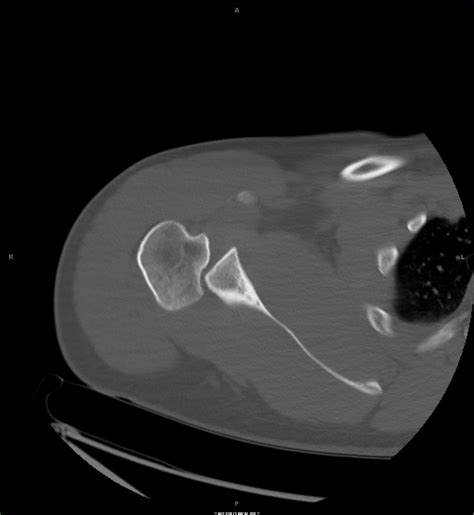

Diagnosing posterior shoulder dislocation involves a combination of physical examination and imaging tests. The diagnostic process typically includes:

• Physical Examination: A healthcare provider will assess the shoulder for deformity, swelling, and range of motion.

• Imaging Tests: X-rays are the primary imaging tool used to confirm the diagnosis. Additional tests such as CT scans or MRIs may be ordered to evaluate the extent of the injury and any associated damage to surrounding tissues.